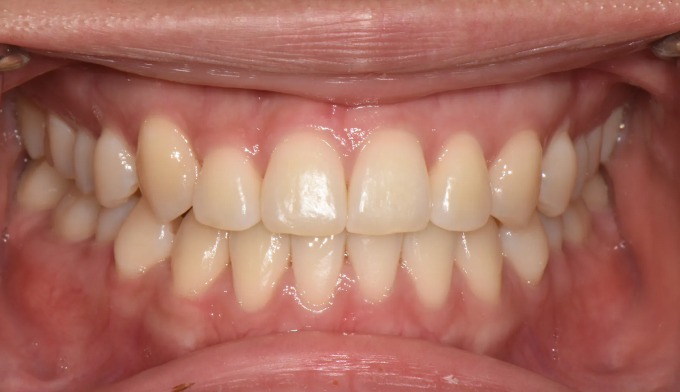

성인에서의 주걱턱은 흔히들 교정치료로 개선 불가능하다고 알고 있습니다. 주걱턱을 해소하기 위해서는 양악수술만이 답이라고 생각합니다.

턱의 성장이 과도하여 안모의 개선이 필요한 경우, 또는 치아가 이동해야할 양이 교정치료로 가능한 양보다 너무 큰 경우를 제외하고 대부분의 주걱턱 또는 반대교합은 교정치료로 해결이 가능합니다.

주걱턱이라고 하여 내원하신분들 대부분 위턱과 아래턱의 비율은 정상이지만 앞니만 반대로 물리는 반대교합의 경우가 많습니다. 어렵지않게 앞니를 배열하여 보다 더 매력적인 미소를 갖는 얼굴을 만들어줄 수 있습니다,

총 치료기간은 15개월 소요되었습니다.

거꾸로 물려있던 앞니를 앞으로 보내면서, 아래치열은 사랑니발치 후 미니스크류를 이용하여 후방이동시켰습니다.